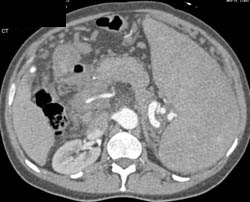

Polyarteritis Nodosa